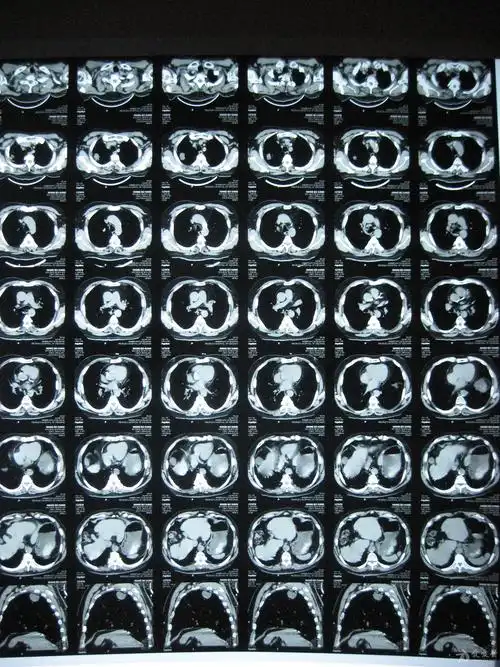

经典肺ct展示